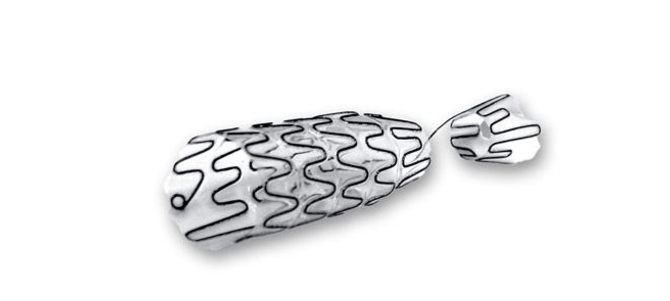

Ουρολογικά

Εξειδίκευση, καινοτομία, αποκλειστικότητα

Με πολυετή εμπειρία στον τομέα της ουρολογικής χειρουργικής, η L&B Medical αποτελεί σταθερό συνεργάτη της ιατρικής κοινότητας.

Προσφέρουμε μια επιλεγμένη σειρά προϊόντων που ανταποκρίνονται στις απαιτήσεις της καθημερινής κλινικής πράξης αλλά και των πλέον εξειδικευμένων επεμβάσεων, συνδυάζοντας ασφάλεια, εργονομία και τεχνολογική υπεροχή.

Στην κατηγορία Ουρολογικά, θα βρείτε επιλεγμένα προϊόντα υψηλής ποιότητας, σχεδιασμένα για:

• Ταχύτερη αποκατάσταση

• Βελτίωση της ποιότητας ζωής του ασθενή, μέσω καινοτόμου σχεδίασης

• Μείωση του ρίσκου επανεμφάνισης στενώσεων

Δείτε αναλυτικά τα προϊόντα μας και ανακαλύψτε την ποιότητα που μας καθιστά αξιόπιστο συνεργάτη σε δημόσια νοσοκομεία και ιδιωτικές κλινικές.

1. Ουρητηρική ενδοπρόθεση (URS) για Παλίνδρομη ή Ορθόδομη χρήση

2. Ενδοπρόθεση βολβικής ουρήθρας

3. Ενδοσκοπική τριγωνική ενδοπρόθεση (TPS) από Nitinol για προστατική ουρήθρα

4. Ενδοπρόθεση για στένωση του αυχένα της κύστης (RPS)